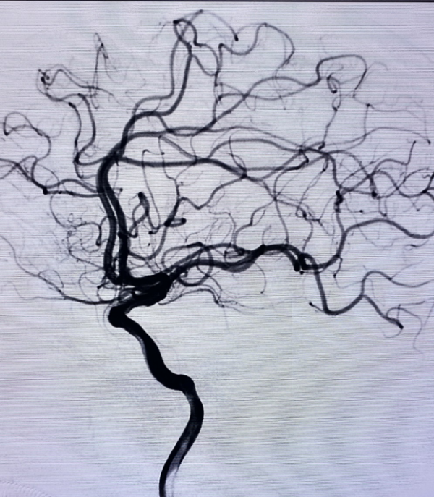

术后影像

导丝怎么扩【载药时代 球扩天下】NOVA DES®颅内药物洗脱支架在大脑中动脉重度狭窄中的应用两例!_https://www.jmylbn.com_新闻资讯_第22张

导丝怎么扩【载药时代 球扩天下】NOVA DES®颅内药物洗脱支架在大脑中动脉重度狭窄中的应用两例!_https://www.jmylbn.com_新闻资讯_第23张

术后正位

术后侧位

术后复查,患者未再发生发作性头晕、右侧肢体无力及言语含混情况,情况良好,无特殊不适主诉。